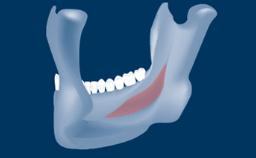

- postoperative complications of sinus floor elevation